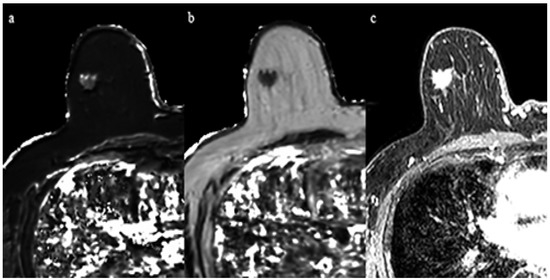

3.2. Relationship with ER Status

Clinical and pathological characteristics, and quantitative MRI values for the 29 lesions are shown in Table 1. No statistical significance was found between the ER-positive cancers and the ER-negative cancers regarding age and tumor diameter. The Ki-67 of ER-negative cancers was significantly higher than that of ER-positive cancers (p < 0.05). Mean T2 relaxation of ER-negative cancers (92.1 ± 13.0 msec) was significantly higher than that of ER-positive cancers (72.7 ± 15.7 msec, p = 0.01) (Figure 1, Figure 2 and Figure 3). Mean T1 relaxation and PD of ER-negative cancers were higher than those of ER-positive cancers, but no significant difference was observed between them. The AUCs of T1, T2, and PD for the differentiation of ER-negative cancers from ER-positive cancers were 0.74 (95% confidence interval (CI): 0.54–0.88), 0.87 (95% CI: 0.69–0.97), and 0.62 (95% CI: 0.42–0.79), respectively. The T2 value had the highest AUC, followed by T1 and PD. The optimal sensitivity and specificity of the T2 value were 100% and 78%.

Figure 3. A 69-year-old woman with invasive ductal carcinoma in the right breast. Immunohistochemical staining showed positivity for estrogen receptor and Ki-67 of 10%. (a) T1 map shows an intermediate signal mass. Mean T1 of the mass was 986 msec. (b) T2 map shows a low signal mass. Mean T2 of the mass was 61 msec. (c) Corresponding contrast enhanced MR image.